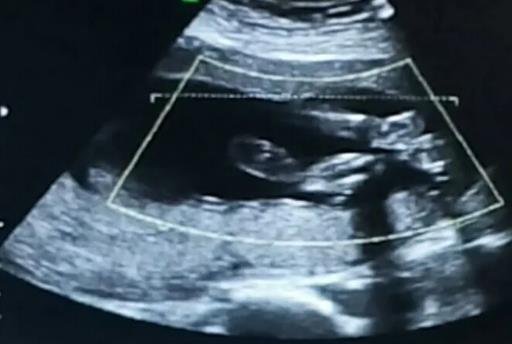

1、看字母

彩超單頂頭最右邊有兩行字,由英文字母和數(shù)字組成,第一行是日期,第二行是時(shí)間,如果第一行是M開(kāi)頭,那就是男(male),如果是F開(kāi)頭,那就是女(female),第二行打頭T是時(shí)間的意思。

2、看有沒(méi)有“腎盂分離”

在彩超檢查單上看看有沒(méi)有“雙側(cè)腎盂分離”這幾個(gè)字,如果有的話,那很有可能是男寶寶,因?yàn)槟袑殞毜纳斫Y(jié)構(gòu)容易出現(xiàn)尿潴留的現(xiàn)象,導(dǎo)致出現(xiàn)腎盂分離,只要沒(méi)有超過(guò)10mm就是正常的。

3、看胎心率

一般來(lái)說(shuō)女孩的胎心率會(huì)高于男孩,男孩的胎心率一般在140左右,女孩的胎心率在150左右。

4、看孕囊形狀

如果孕囊形狀呈長(zhǎng)條形,那么有可能懷的是男寶寶;如果孕囊形狀呈現(xiàn)圓形或類似橢圓形,則女孩的可能性大一些。

小編提示:這些訣竅只是一種概率,并不準(zhǔn)確,我國(guó)法律規(guī)定醫(yī)生不準(zhǔn)提前告知嬰兒性別,所以各位準(zhǔn)爸準(zhǔn)媽還是把孩子的性別當(dāng)成一個(gè)驚喜來(lái)對(duì)待吧。